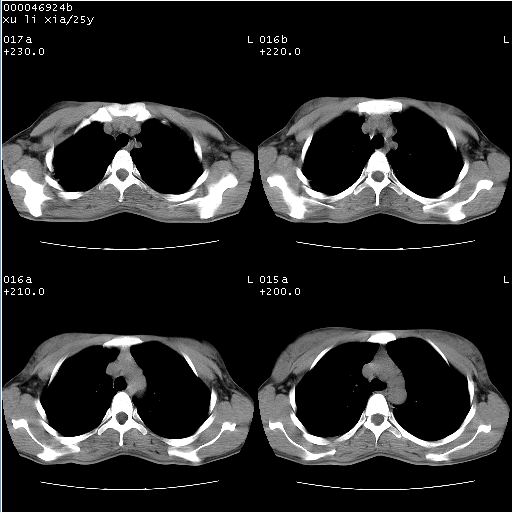

患者 女,25岁。因“左侧卵巢肿瘤”术前胸片偶然发现两肺病变。平素无明显不适,无呼吸系统症状及体征,无传染病史。

胸部ct轴位平扫(层厚10mm,螺距1.5,重建间隔10mm),图像如下:

病灶呈地图样分布于肺外围,与正常组织分界清晰+弥漫性磨玻璃影中见小叶间隔增厚呈碎石路样表现+年轻女性,无明显临床症状=肺泡蛋白沉积症?

双肺病灶以渗出影搀杂斑点状阴影为主,部分阴影融合成团片,并沿纹理明显见播散灶。支持楼主:两肺感染性病变(结核可能性大)!

双肺上叶可见节段性渗出性病变,可见树芽征像,左肺下叶背段可见结节影。

病灶呈离心性分布,以两上肺多见,远离肺血管纹理,有部分肺间质条索影,病人症状轻微,考虑结节病。